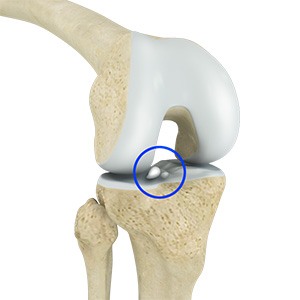

Loose Bodies in the Knee

Loose bodies are fragments of detached cartilage or bone inside the knee joint. These fragments may be free floating (unstable) or may be trapped (stable) within the joint. Depending on the severity, you may have one or more loose bodies in your knee joint.